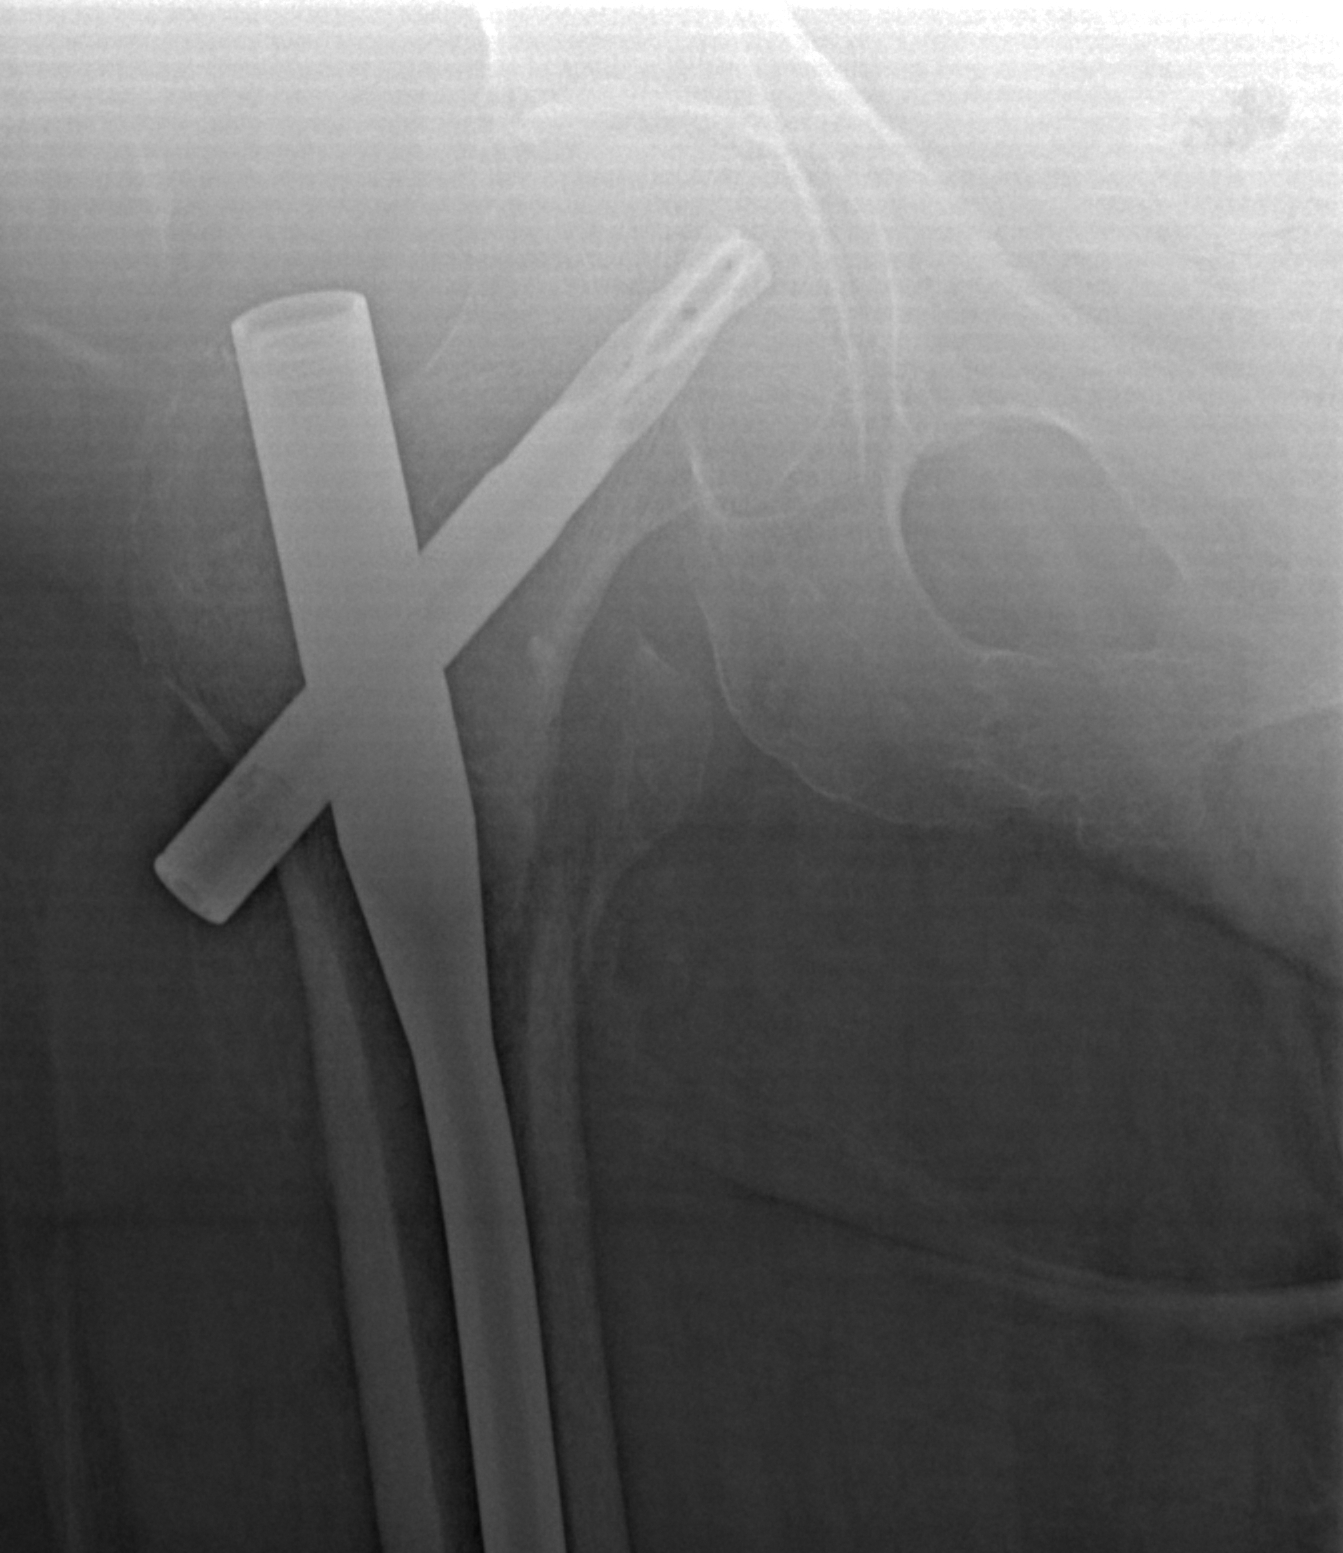

Правый тазобедренный сустав